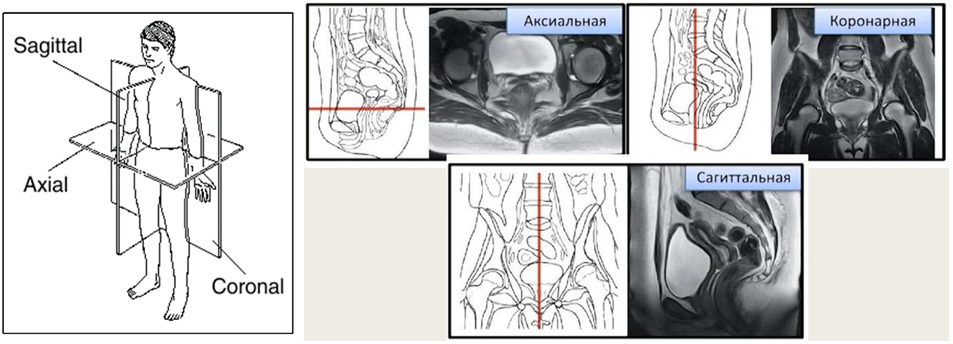

Еще один важный общий для всех томографий термин – проекция. Это плоскость, параллельно которой располагаются слайсы:

-

Ax, Axial, Tra, Transversal — аксиальная (трансверсальная) проекция;

-

Sag, Sagittal — сагиттальная проекция;

-

Cor, Coronal, Frontal — коронарная (фронтальная) проекция.

Наряду с прямыми проекциями, встречаются и «косые» (oblique), которые располагаются под разными углами.

Часто в рамках одного исследования формируется несколько наборов различных проекций. При отсутствии одной или двух они могут быть математически сформированы из имеющихся – с погрешностями, но достаточно наглядно для визуального анализа. Пригодность таких восстановленных проекций для обучения нейронных сетей стоит оценивать в зависимости от решаемой задачи и имеющегося набора данных.